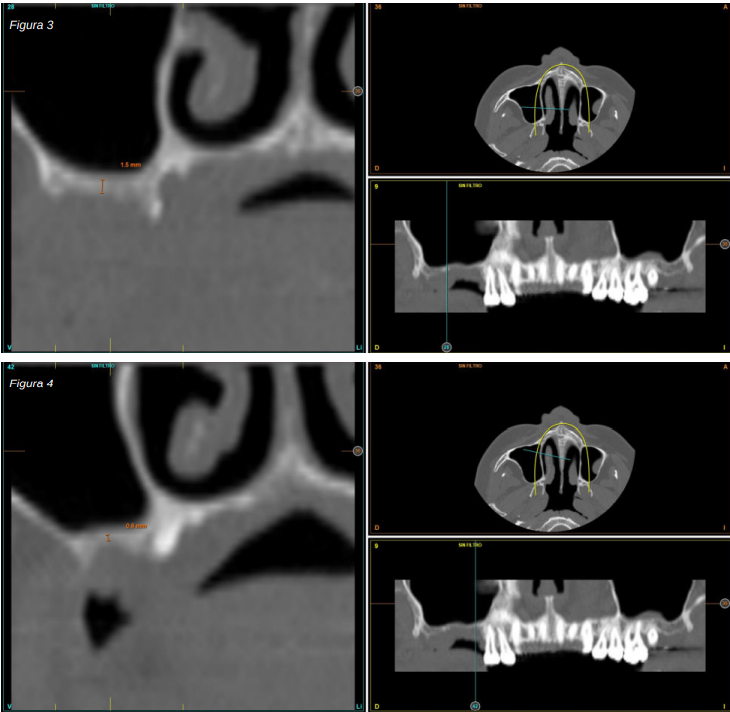

Se realiza la extracción de ambos y la regeneración de los alveolos con PRGF-Endoret para lograr el sellado de la perforación y una evolución lo más favorable posible para la posterior inserción de los implantes en la zona. Tras dos meses podemos observar en el Cone-Beam dental que la perforación se ha cerrado completamente pero el volumen óseo residual en altura para la inserción de los implantes es insuficiente, existiendo únicamente un 2 mm de altura ósea (Figuras 3 y 4).